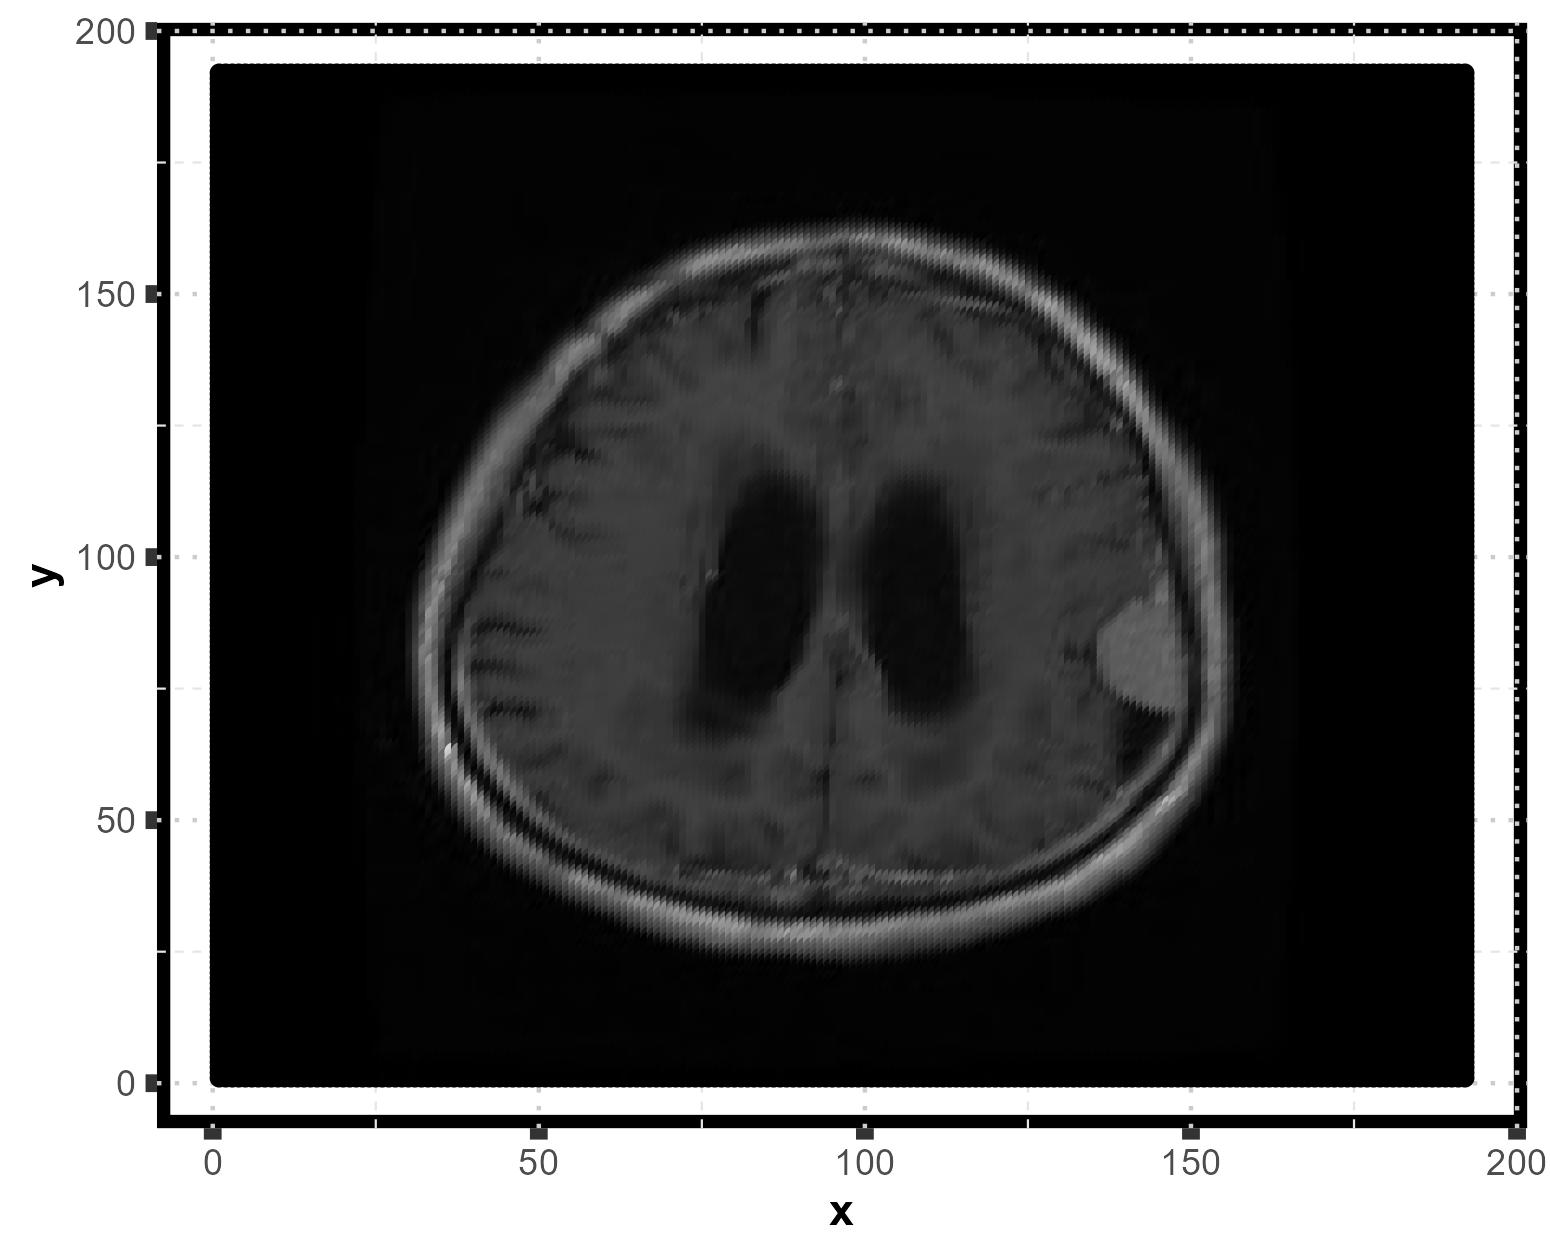

Brain MRI: tumor detection

Ref: https://www.kaggle.com/datasets/masoudnickparvar/brain-tumor-mri-dataset